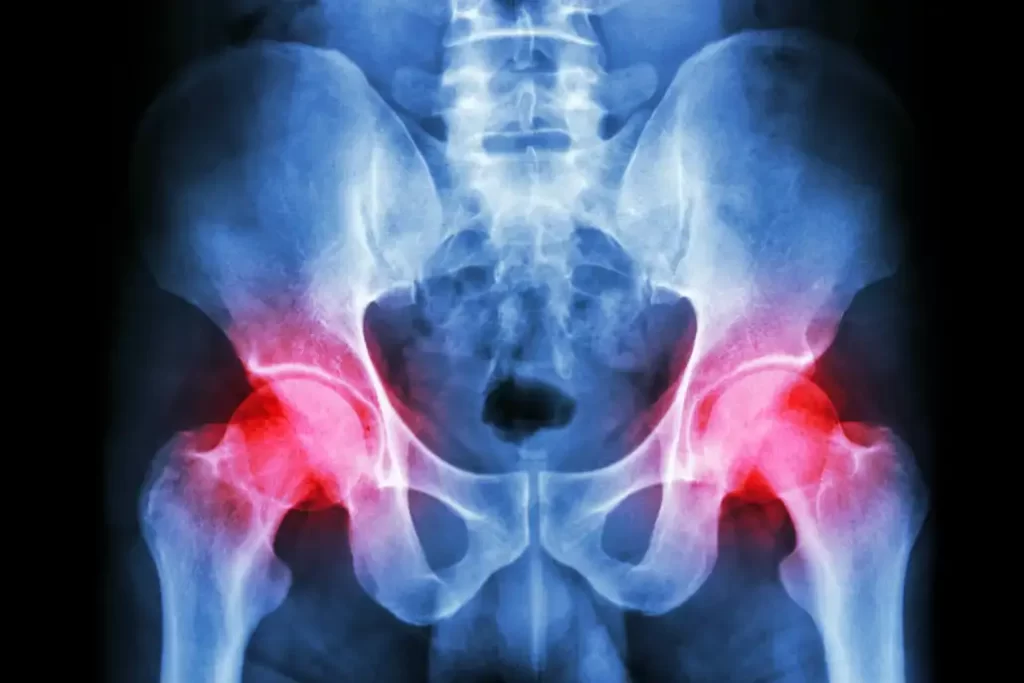

تشخیص آرتروز لگن با ترکیبی از معاینهٔ بالینی و تصویربرداری انجام می‌شود. دکتر عبدالرضا افشاریان در معاینه، به حرکت‌پذیری مفصل، نقاط دردناک و وضعیت راه‌رفتن شما توجه می‌کند. سپس برای تایید تشخیص، یک رادیوگرافی (عکس سادهٔ لگن) درخواست می‌شود که نشان می‌دهد آیا فضای بین استخوان‌ها کم شده یا خیر و آیا خارهای استخوانی (استئوفیت) تشکیل شده‌اند.

در موارد پیچیده‌تر، ممکن است از MRI یا سی‌تی‌اسکن نیز استفاده شود تا وضعیت دقیق‌تر غضروف و بافت‌های نرم بررسی شود.